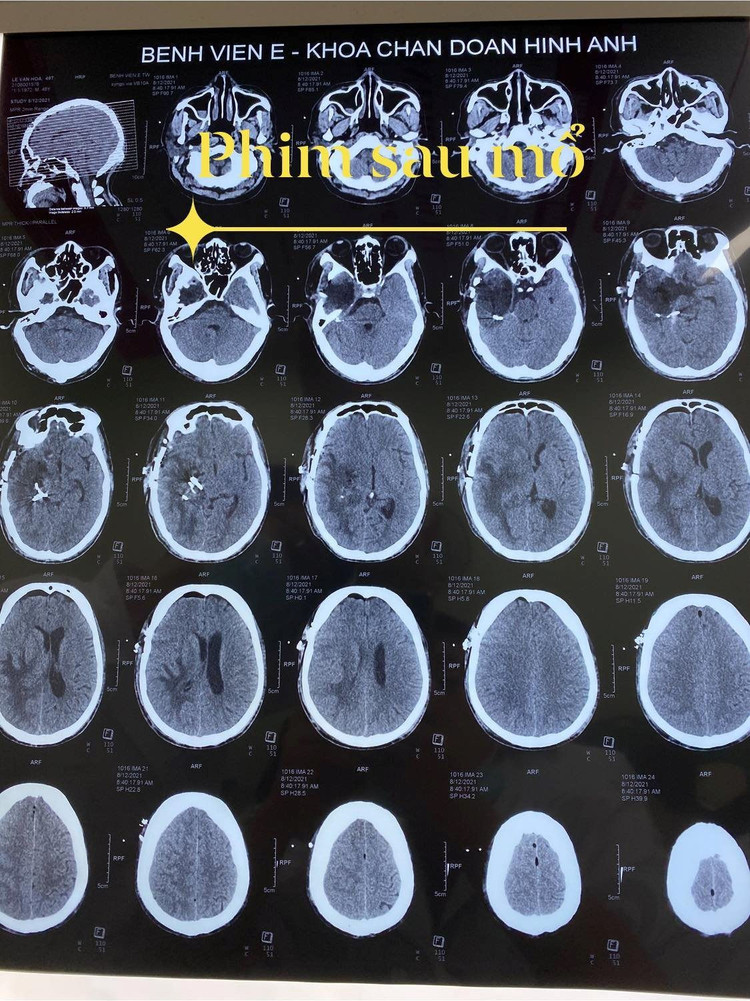

Khối u đã được lấy hết sau mổ.

May mắn sau 5 tiếng, ca mổ đã thành công, khối u đã được lấy toàn bộ, mà không có biến chứng đáng kể nào. Sau mổ 1 ngày, triệu chứng đã cải thiện rất nhiều, bệnh nhân đỡ đau đầu, vận động đi lại bình thường, không yếu liệt.